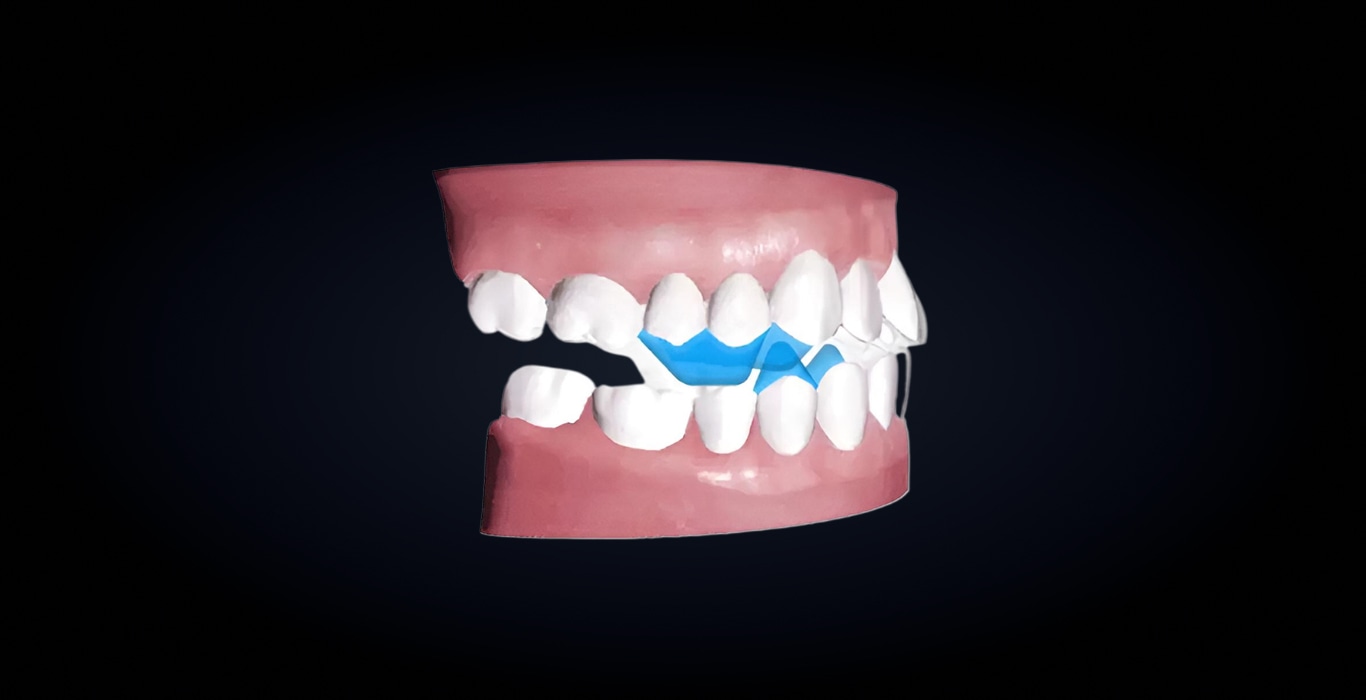

Объединяет в один процесс два этапа функционального ортодонтического лечения: выдвижение нижней челюсти и выравнивание зубов. Позволяет перемещать зубы и одновременно с этим корректировать окклюзионное соотношение, что повышает эффективность и сокращает длительность лечения.

Благодаря специально спроектированным окклюзионным блокам достигается контролируемое выдвижение нижней челюсти, а автоматизированный запрограммированный дизайн блоков исключает необходимость их коррекции вручную во время лечения.